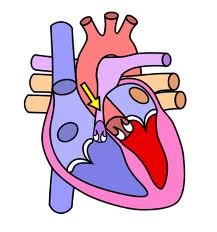

În funcție de locație, se poate dezvolta supravalvulara, valve si stenoza subvalvulara, artera pulmonară, dar este de restricție cel mai frecvent in zona supapei (90%).

Stenoza se dezvoltă ca urmare a încălcării formării valvei pulmonare, care nu se dezvoltă clapele sale și clapa are forma orificiului.

Când dezvolta stenoza, format diferență (gradient) dintre presiunea din ventriculul drept si artera pulmonara. În funcție de amploarea valorilor tensiunii arteriale și cât de mare gradientul în sine, oferind 4 trepte stenoză.

stenoza pulmonară poate fi determinată la făt în timpul sarcinii. Pentru a face acest lucru, să efectueze ultrasunete și de studiu cu raze X. hipertrofia gestational (creșterea în mărime) a ventriculului drept al inimii.